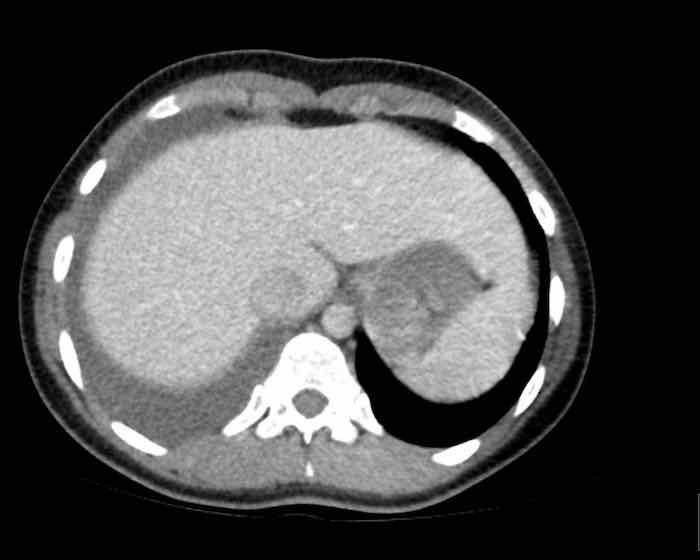

Đây là hình ảnh của một nam giới 24 tuổi.

Hãy quan sát kỹ các hình ảnh trước.

Câu hỏi: đây có phải là tuyến ức bình thường không?

Hình ảnh

Mặc dù tuyến ức này khá lớn, nhưng có hình tam giác bình thường và chứa mỡ (mũi tên).

Đây là tuyến ức bình thường.